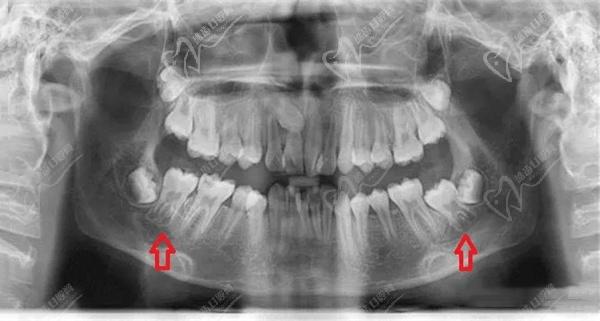

2、牙髓腔扩大:通过X线检查可以发现,牛牙症患者的牙髓腔明显扩大。这是由于在牙齿发育过程中,牙髓腔的发育与牙齿形态发育不匹配所导致的。

2)牙髓腔扩大:通过X线检查可以发现患者的牙髓腔明显扩大,尤其是在根尖部。

3)牙髓底部顶 端位移:X线检查显示牙髓底部向上位移,导致牙髓腔底部与牙齿顶部之间的距离增加。